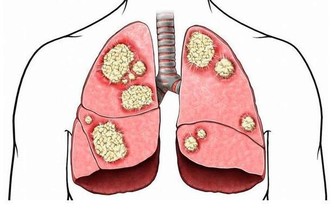

4.骨科醫生:吃補鈣藥不如吃含鈣食物

食補比藥補更有效用,真的想要改善自己的骨骼健康,日常的飲食就要做起,

成年人每天適宜攝取800毫克的鈣量,這些都可以從食物中取得,

像是芝麻、海帶、蝦皮、牛奶、乳酪、芥菜、海參和豆製品等等,

飲食配上運動才是身體健康的不二法門。